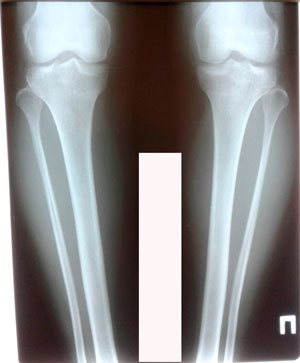

перед крутками

Вложения

image-12-03-20-09-54.jpg